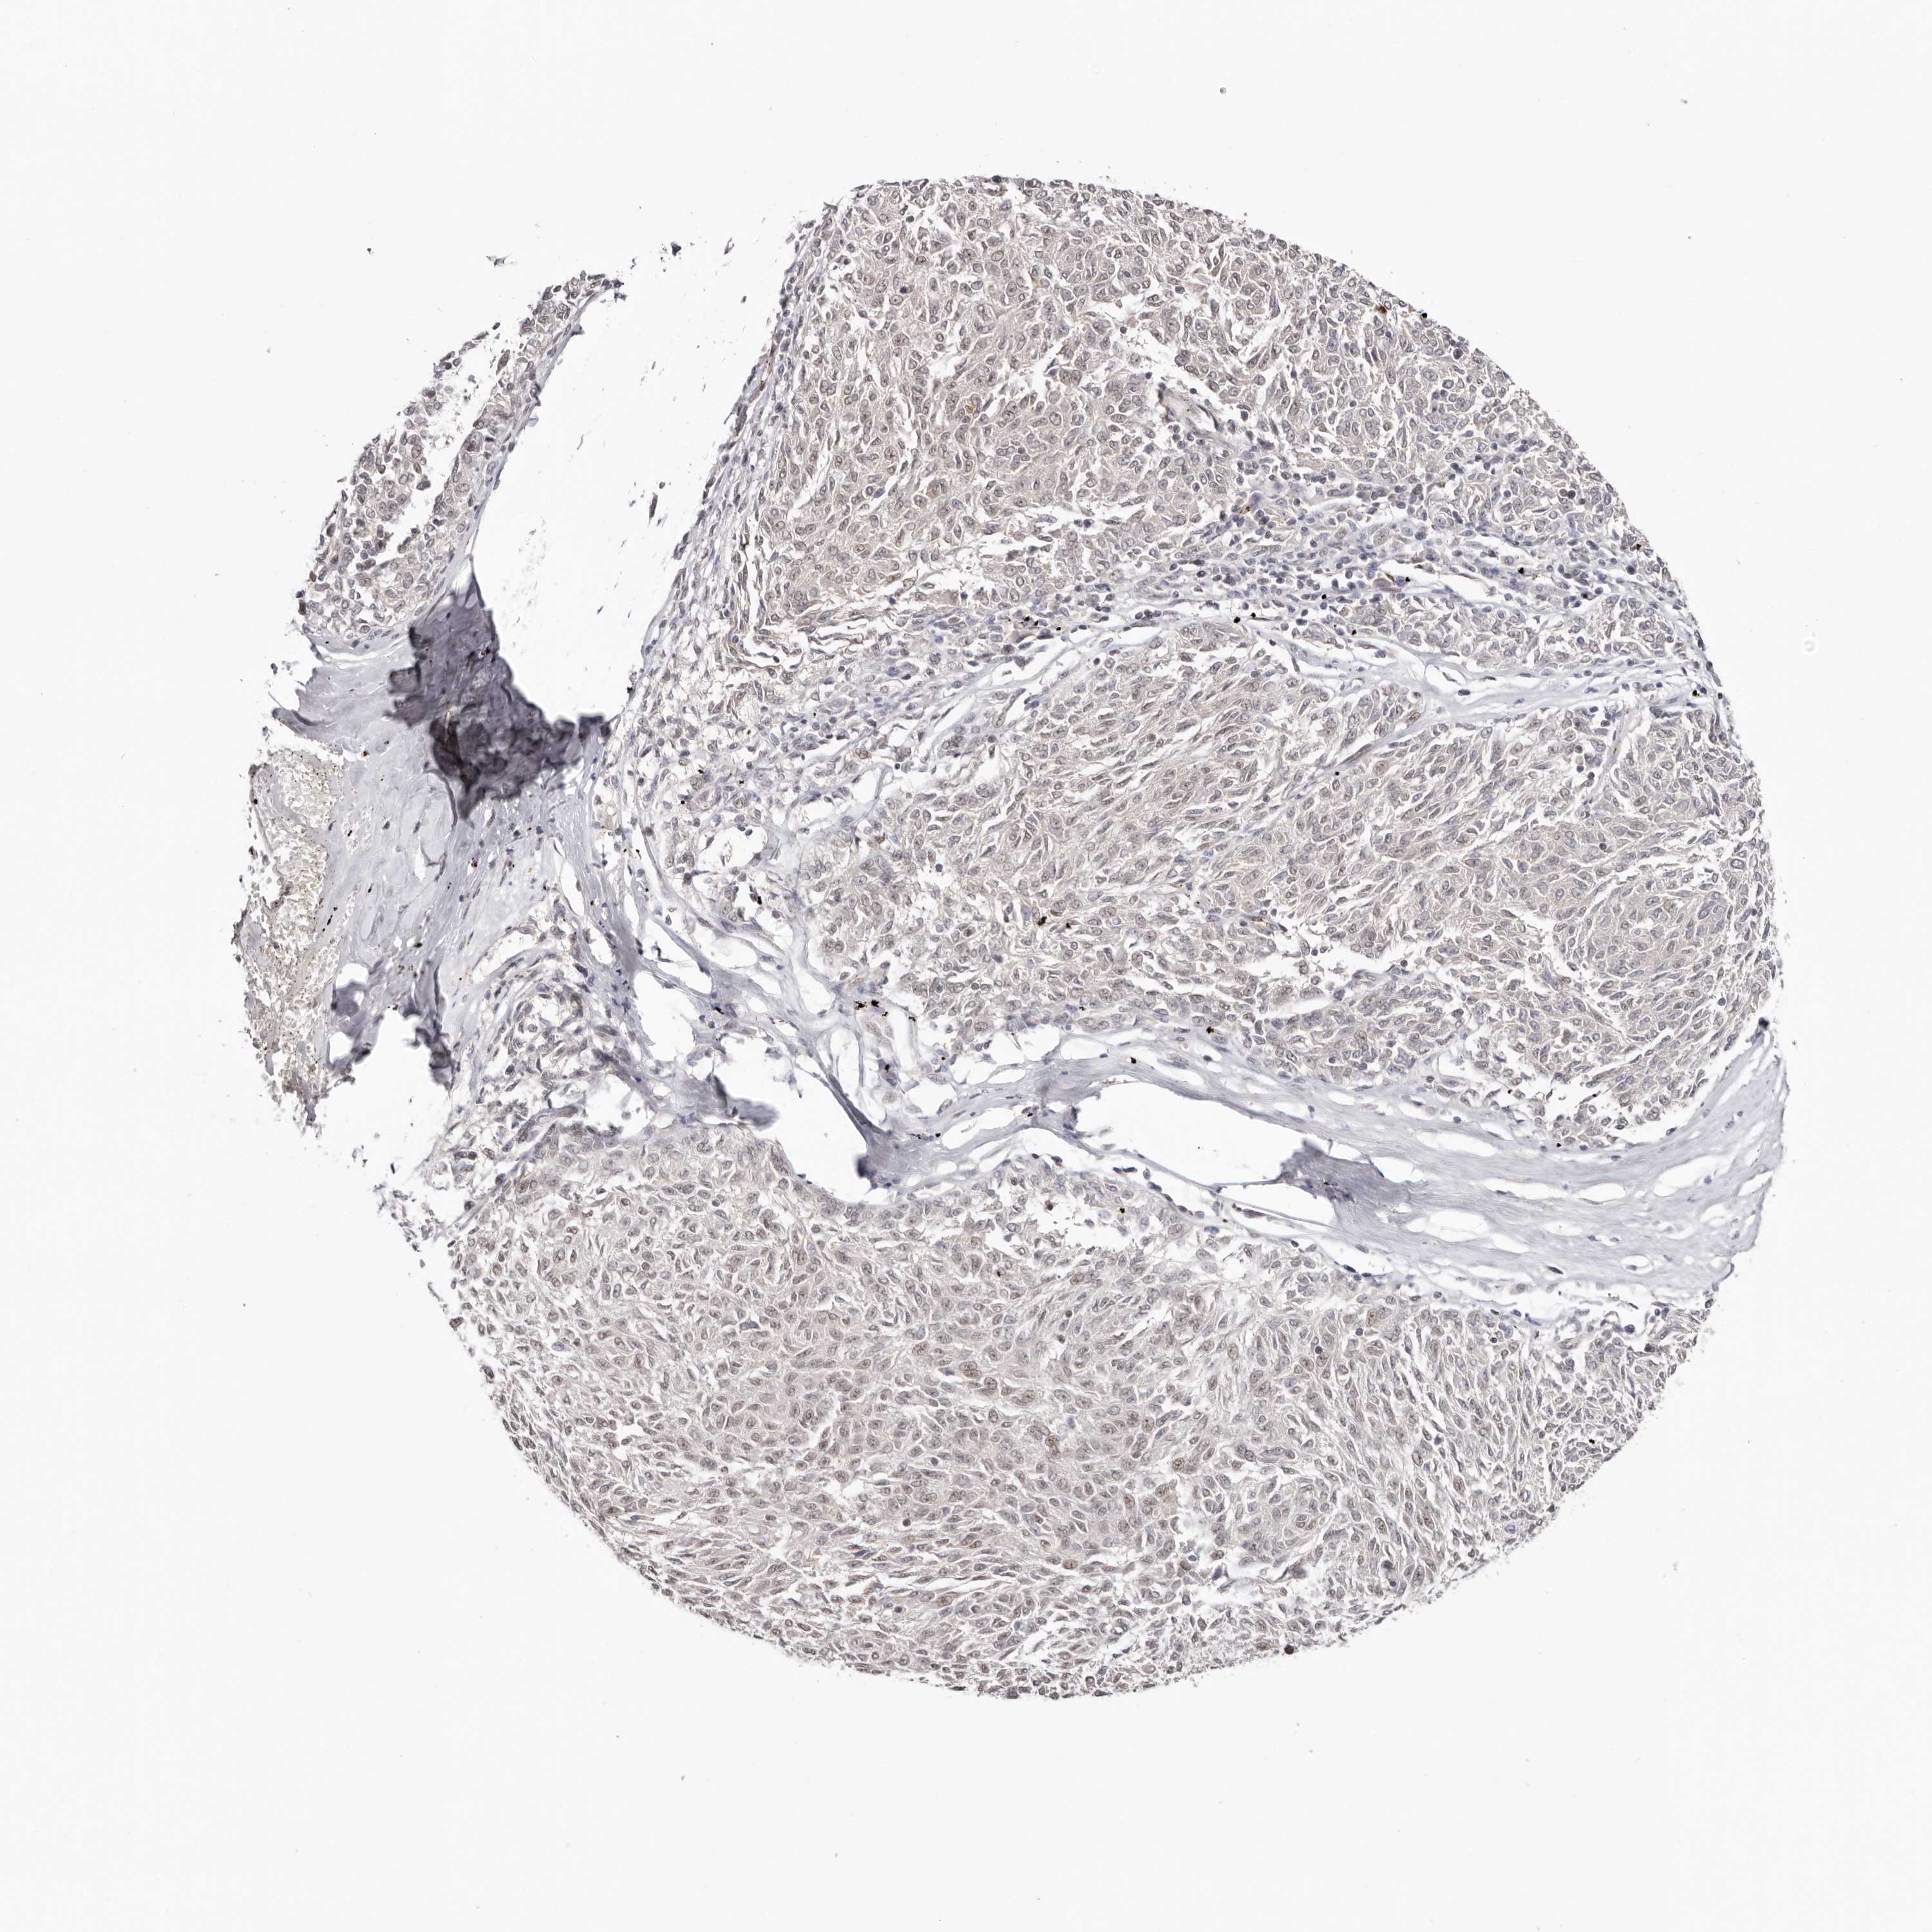

MELANOMA - Protein expressioni

A mouse-over function shows sample information and annotation data. Click on an image to view it in a full screen mode. Samples can be filtered based on level of antibody staining by selecting one or several of the following categories: high, medium, low and not detected. The assay and annotation is described here.

Note that samples used for immunohistochemistry by the Human Protein Atlas do not correspond to samples in the TCGA dataset.

Antibody stainingi

Antibody staining in the annotated cell types in the current human tissue is reported as not detected, low, medium, or high, based on conventional immunohistochemistry profiling in selected tissues. This score is based on the combination of the staining intensity and fraction of stained cells.

Each image is clickable and will lead to virtual microscopy that enables deeper exploration of all samples and also displays staining intensity scores, fraction scores and subcellular localization as well as patient and tissue information for each sample.

Antibody HPA028897

Antibody CAB026212

Staining

High

Medium

Low

Not detected

Intensity

Strong

Moderate

Weak

Negative

Quantity

>75%

75%-25%

<25%

None

Location

Nuclear

Cytoplasmic/membranous

Cytoplasmic/membranous,nuclear

Malignant melanoma, NOS

Malignant melanoma, Metastatic site